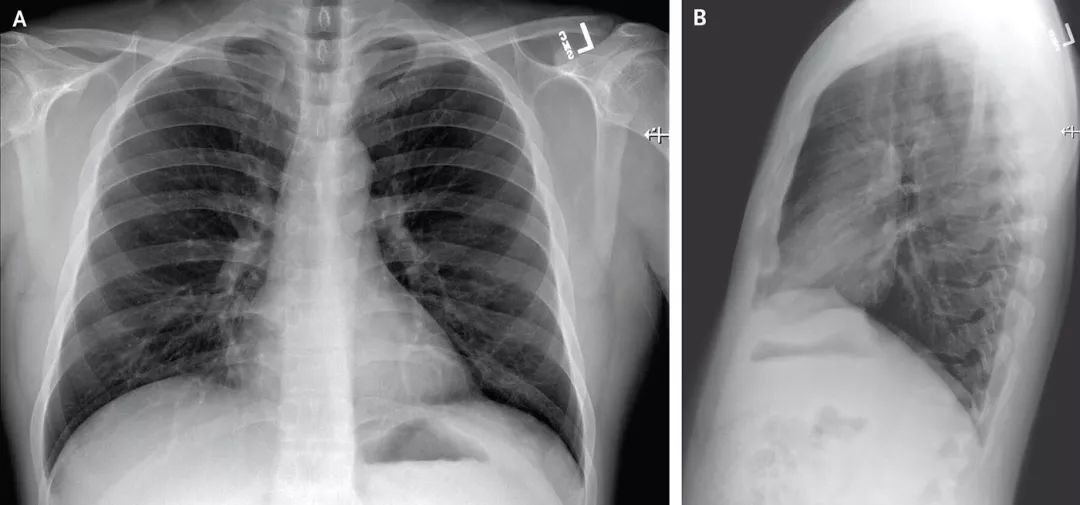

与试剂盒相比,CT检查最大的优势是快,在武汉当前的疫情下,胸部CT的影像观察,方便、快捷、直观,能够快速判断疾病程度。

这里我要先提醒一件总是被媒体、被公众忘记的一件事,胸部CT双肺白色病变(X光就是“大白肺”),那肯定是肺炎啊。

不管是新冠病毒引起的“非典型性”肺炎,还是流感病毒、腺病毒等引起的普通病毒性肺炎(间质性炎症),再或者是细菌性肺炎(实质性炎症),那都是肺炎啊,都有可能死人,都是严重疾病得治疗啊!

在发烧38.7℃,胸部CT检查显示双肺下叶感染、血常规也符合病毒感染相关指标的情况下,已经可以判断病毒性肺炎。